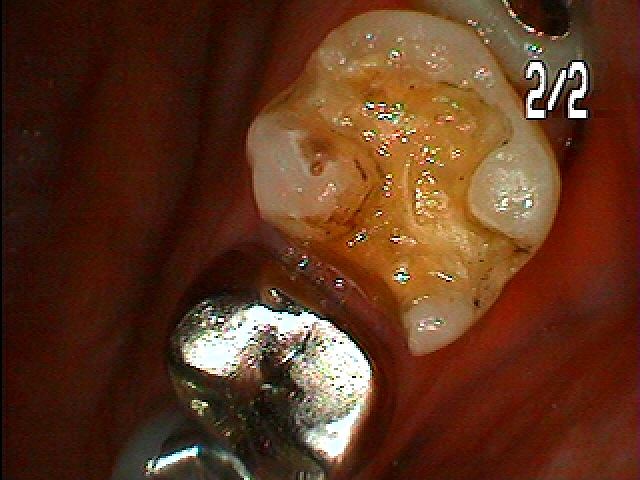

問題の歯になります

中は黒く虫歯にもなってきていました